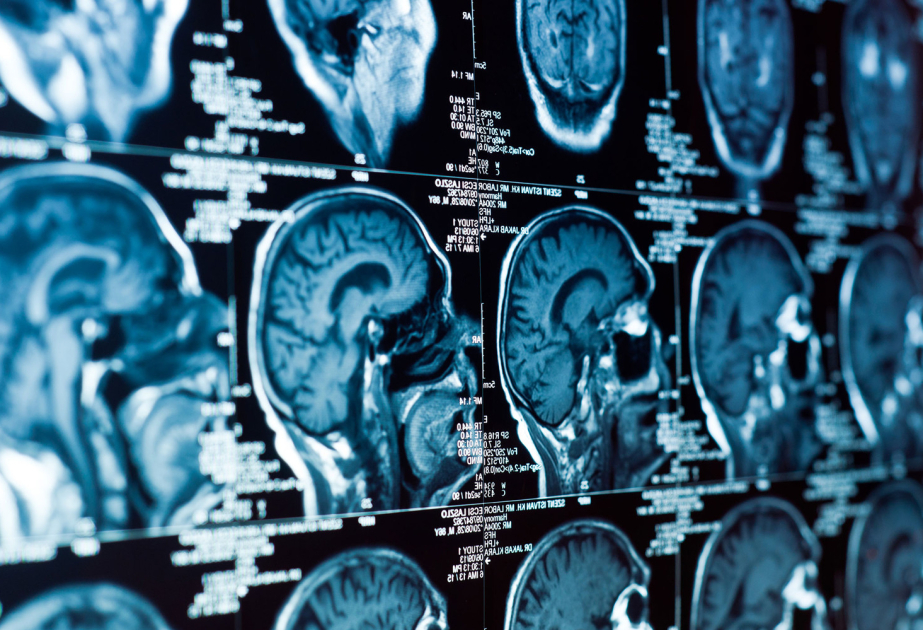

İsveçrənin Sürix və ABŞ-ın Nyu-York universitetlərinin tədqiqatçıları beyin¬də eyni anda bir neçə sahəni yüksək dəqiqliklə ultrasəs vasitəsilə stimullaşdırmağa imkan verən texnologiyanı təqdim ediblər.

İndiyədək ultrasəs neyromodulyasiyası yalnız bir nöqtəyə təsir göstərməyə imkan verirdi və bu da məhdud səmərəliliklə, həmçinin yüksək yan təsir riski ilə müşayiət olunurdu. Yeni cihaz isə yüzlərlə miniatür ötürücüdən ibarətdir. Onların yaratdığı ultrasəs impulsları bir-biri ilə üst-üstə düşərək hologramdakı işıq dalğalarını xatırladır. Nəticədə beyində bir neçə fokus nöqtəsi yaranır və neyron şəbəkələri aktivləşir.

Layihəyə rəhbərlik edən professor Daniel Razanskinin sözlərinə görə, bir neçə zonaya eyni vaxtda təsir imkanı ultrasəsin daha zəif intensivlikdə istifadəsinə şərait yaradır ki, bu da metodu daha təhlükəsiz edir. Əvvəllər təsir çox zəif olduqda stimulyasiya faydasız olurdu, həddindən artıq güclü olduqda isə bütün beyinə təsir edir və toxumalara zərər verirdi.

Texnologiya siçanlar üzərində sınaqdan keçirilib. Heyvanlara kəllə sümüyü üzərindən qeyri-invaziv stimulyasiya aparılıb və neyron şəbəkələrinin aktivliyi qeydə alınıb. Alimlərin ehtimalına görə, ultrasəsin təsiri təkcə lokal zəif istiləşmə ilə deyil, həm də neyronların ion kanallarına mexaniki təsirlə bağlıdır.

Hazırda metod fundamental tədqiqat mərhələsindədir, lakin gələcəkdə Altsheymer xəstəliyi, epilepsiya, tremor, Parkinson xəstəliyi və depressiyanın müalicəsində tətbiq oluna bilər.